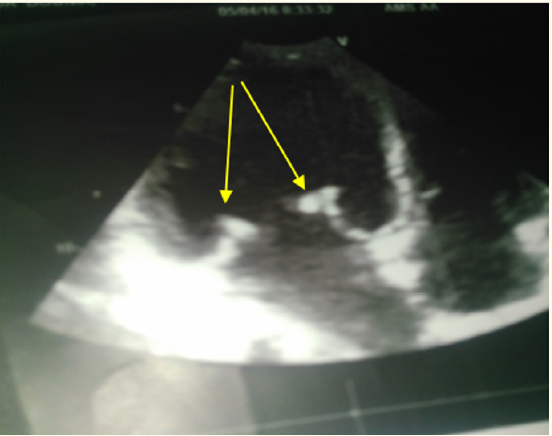

Right Ventricular Myxoma Obstructing RV Inflow and Causing Pulmonary Embolism: Management and Brief Review

Sukhvinder Singh, Mohammad Mubeen and Sanskriti Bhardwaj. 10(1): 37-41.